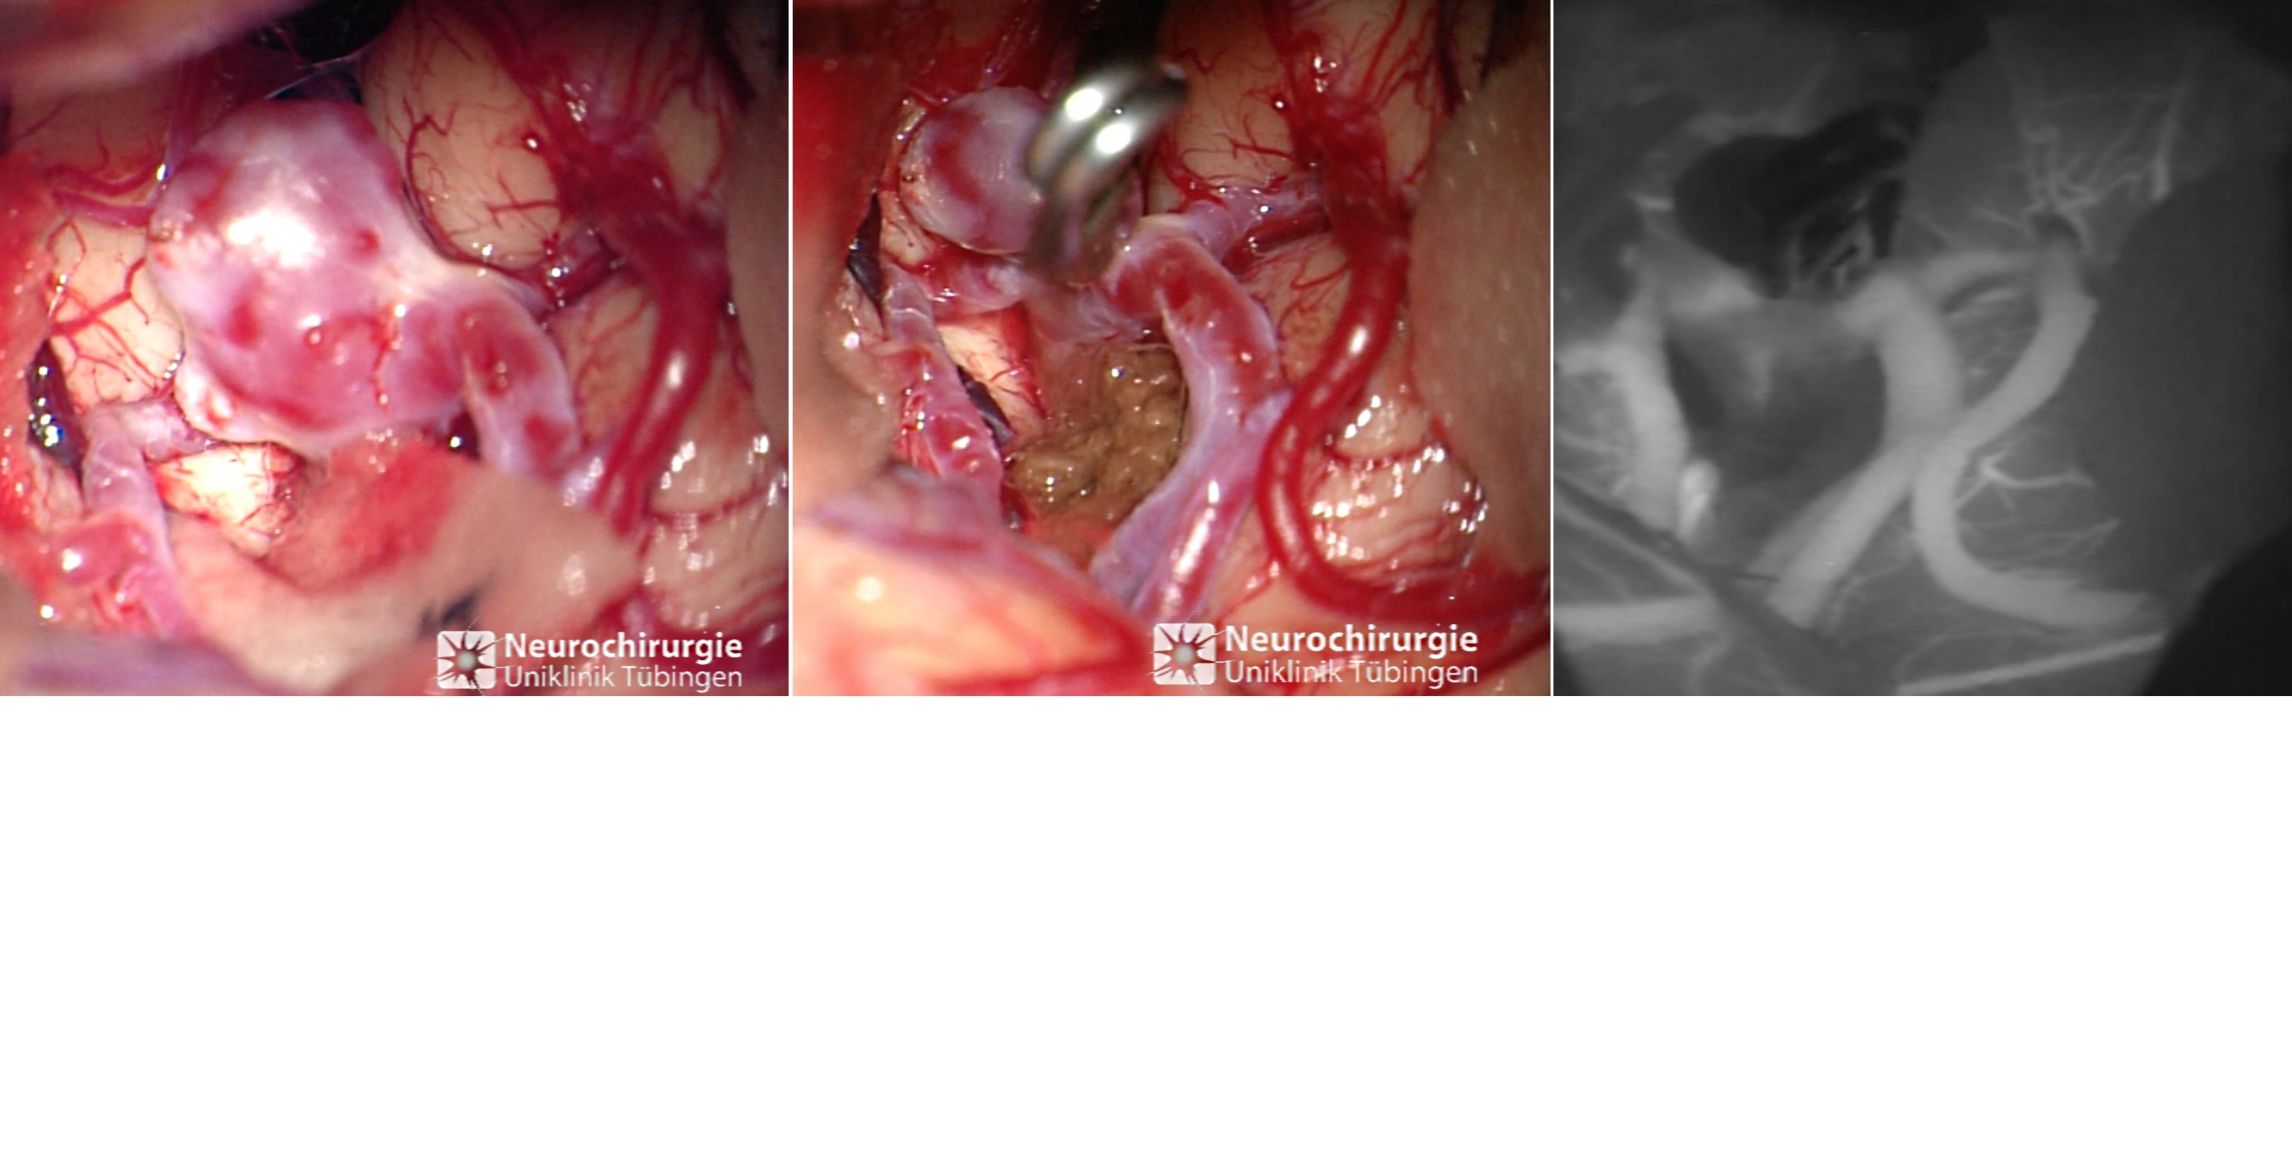

Intraoperatives Bild eines Aneurysmas

Intraoperatives Bild eines Aneurysmas vor (links) und nach (Mitte) dem Clipping. Rechts sieht man in der ICG Angiographie die vollständige Ausschaltung des Aneurysmas.